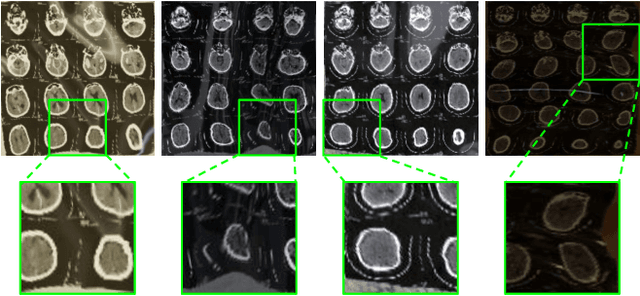

While medical images such as computed tomography (CT) are stored in DICOM format in hospital PACS, it is still quite routine in many countries to print a film as a transferable medium for the purposes of self-storage and secondary consultation. Also, with the ubiquitousness of mobile phone cameras, it is quite common to take pictures of the CT films, which unfortunately suffer from geometric deformation and illumination variation. In this work, we study the problem of recovering a CT film, which marks the first attempt in the literature, to the best of our knowledge. We start with building a large-scale head CT film database CTFilm20K, consisting of approximately 20,000 pictures, using the widely used computer graphics software Blender. We also record all accompanying information related to the geometric deformation (such as 3D coordinate, depth, normal, and UV maps) and illumination variation (such as albedo map). Then we propose a deep framework to disentangle geometric deformation and illumination variation using the multiple maps extracted from the CT films to collaboratively guide the recovery process. Extensive experiments on simulated and real images demonstrate the superiority of our approach over the previous approaches. We plan to open source the simulated images and deep models for promoting the research on CT film recovery (https://anonymous.4open.science/r/e6b1f6e3-9b36-423f-a225-55b7d0b55523/).